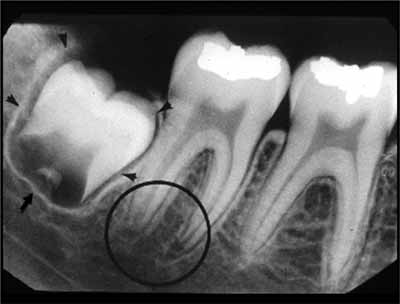

歯の発育がまだ完了していない子供や青少年では、歯列の発育段階に応じて歯の外観が変化すると考えられます。歯根の発達が不完全な歯は根尖性歯周炎に似ている可能性があるため、レントゲン写真で根尖周囲の変化を確認する際には、この点に留意することが重要です (画像4を参照)。

下顎の外側部に向かって後方に移動すると、犬歯、小臼歯、大臼歯が見えます。小臼歯と大臼歯の下には下顎管があり、薄いエックス線不透過性の境界に囲まれた幅広いエックス線透過性の線として現れます。下顎管は下顎の頬側表面にあるオトガイ孔に開口しています。口腔内画像では、オトガイ孔は小臼歯の根尖のすぐ下またはその高さにある丸いエックス線透過性の構造として確認できます(画像 18 および 19 を参照) 。下顎管は下顎枝にあるオトガイ孔から下顎孔まで下顎の外側部分全体に沿って走っています。多くの場合、臼歯の根尖のすぐ下か、同じ高さに位置します。等角投影と軸測投影の両方で、臼歯の頂点に重なって描かれることもあります(画像20と21を参照)。

下顎の臼歯部の舌側には、別の骨の隆起である顎舌骨筋線があります。これは口底筋の付着部も形成し、大部分が大臼歯の根の上にエックス線不透過性の水平線として現れます(画像24を参照)。顎舌骨筋線の太さは個人によって異なるため、X線画像では明瞭に見えたり見えなかったりする場合があります。顎舌骨筋線のすぐ下には、境界が不明瞭なエックス線透過性の領域があります。これは下顎の舌側表面にあるくぼみ、顎下窩です(画像24参照)。